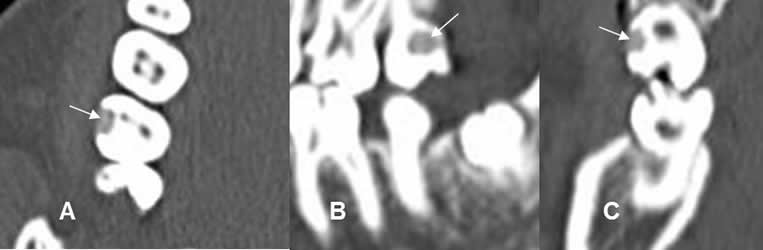

Fig 34. Caries.

A: TAC axial, B: TAC reconstrucción sagital y C: TAC reconstrucción coronal.

Defecto en el cemento del diente, que corresponde a caries.